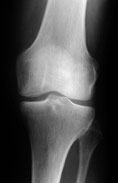

Gesundes Knie Röntgenbild eines gesunden Kniegelenkes mit normalem Gelenkspalt.